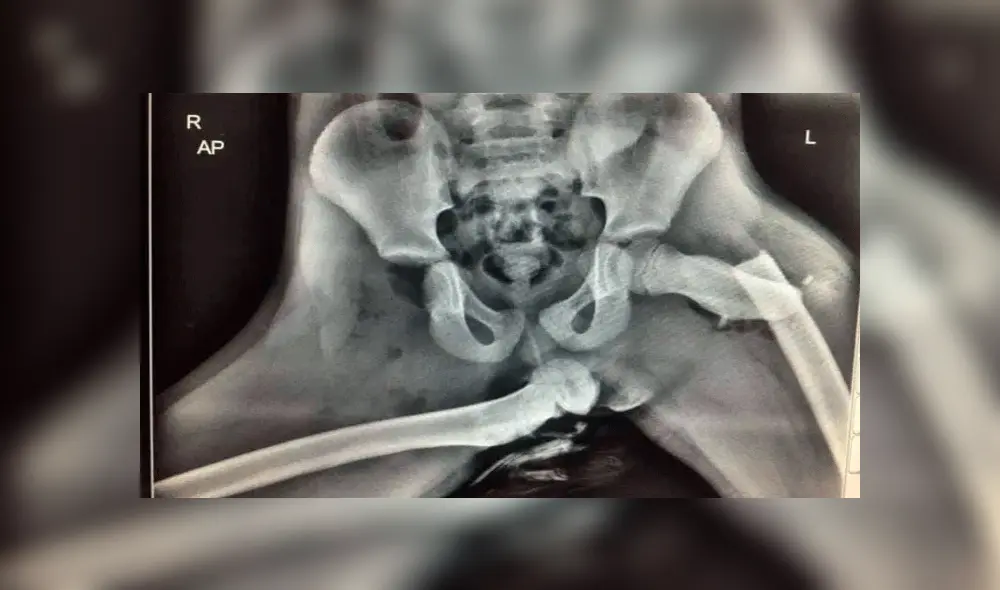

Unas imágenes compartidas por la policía inglesa mostraron las lesiones que sufrió Audra Tatum por llevar los pies sobre el tablero de instrumentos en el momento del choque entre dos vehículos en Gales, Inglaterra.

Tatum se rompió el tobillo, la nariz y el fémur en cuatro partes cuando su esposo perdió el control de auto en el que viajaban y terminó por impactar contra otro vehículo en plena autopista.

La radiografía de Autum circula a través de las redes sociales para que los miles de conductores y pasajeros tomen conciencia. De esta manera, este tipo de accidentes se verán reducidos y menos vidas involucradas.